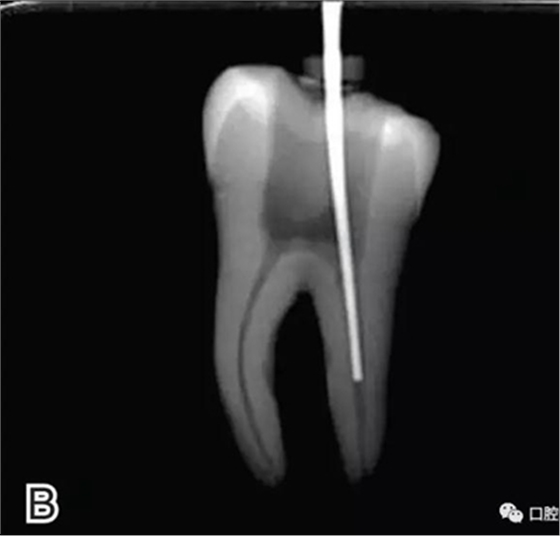

3、試尖

選擇非標(biāo)準(zhǔn)牙膠尖(如0.04、0.06 錐度牙膠尖)作為主尖,型號一般與根管預(yù)備最大號的器械型號一致,能到達(dá)距根尖0.5~1 mm 處,主尖尖段與根管壁緊密接觸。拍試尖X 線片進(jìn)行確認(rèn)(圖3)。

圖3 試尖,A.試主尖 B.拍試尖X片